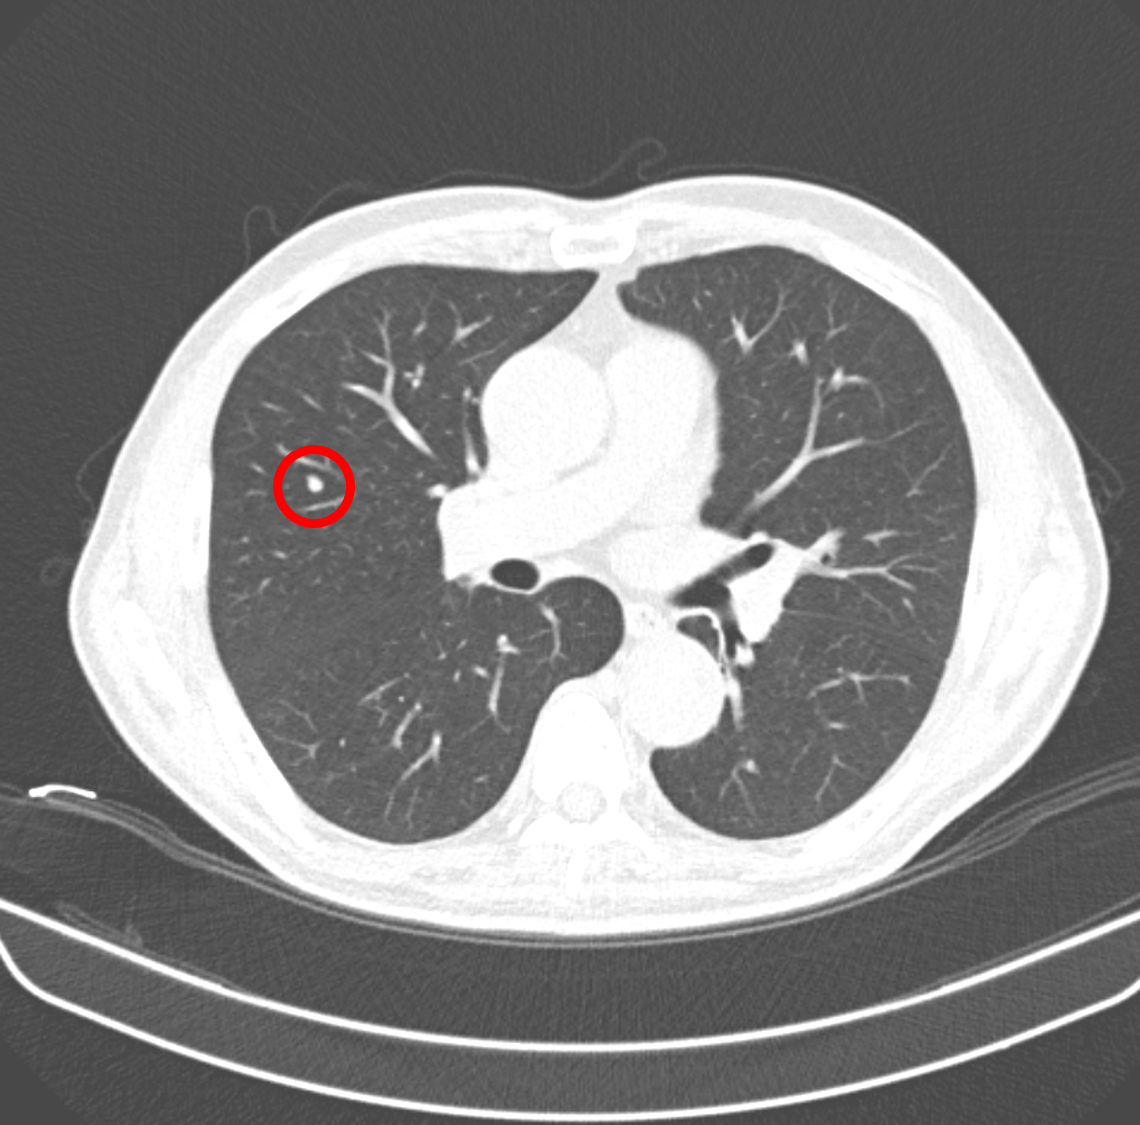

<category 3의 결절. 암일 가능성 1~2%>

과거 판독 결과에는 CT에는 <6mm nodule, Lung-RADS category 3, 경계성 결절. 폐암일 가능성이 1~2% 있으므로, 6개월 후 폐 CT 추적 관찰>이라고 적혀 있었다. 하지만 환자는 6개월 후에 병원에 오지 않았고, 금연도 하지 않았으며, 2년 만에 왔다.

말은 그렇게 말했지만, 마음속으로는 찝찝했다. 암일 가능성이 1~2%이면, 정상일 확률이 98~99%이다. 대부분 category 3의 결절은 6개월 후, CT를 찍으면 크기 변화가 없어 category 2로 떨어진다. 나는 환자를 촬영하러 보내고, 다른 환자를 보느라 김성훈 씨를 잊었다.